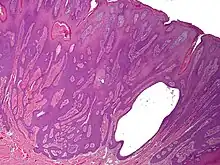

Syringofibroadenoma is a cutaneous condition characterized by a hyperkeratotic nodule or plaque involving the extremities.[1]: 668